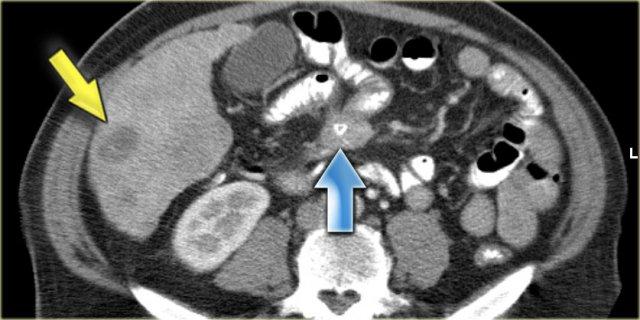

Hình bên trái là bệnh nhân với u carcinoid điển hình có vôi hóa trung tâm (mũi tên xanh dương).

Lưu ý hiện tượng co kéo ruột và dày thành ruột.

Có di căn gan (mũi tên vàng).